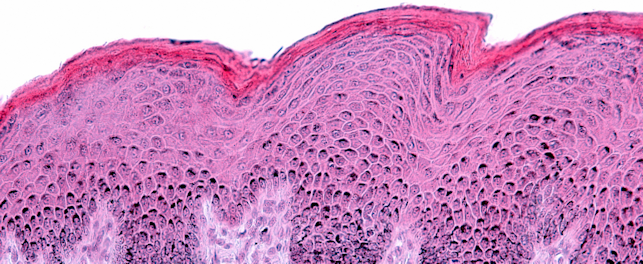

• Microbiological analyses to verify the absence of contamination

• Microbiological analyses: hygiene control, conservation tests